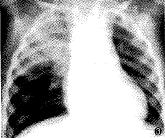

囊状PAVMs通常具有典型X线平片征象,表现为孤立或多发的类圆形阴影,阴影直径大小不等 ,密度均匀,边缘清晰,或有浅分叶;扩张增粗的供血动脉及引流静脉连于阴影,供血动脉 与肺门相连;该阴影一般不增大或仅缓慢增大。根据上述特点,结合临床资料多数囊状PAVM s可作出明确诊断(图1)。不典型者平片诊断有一定困难,例如本组2例复杂型多支供血囊状肺动静脉瘘,平片表现为大片致密影,很难根据X线平片作出正确诊断(图3)。弥漫型肺小动静脉瘘,多缺乏典型X线平片 征象,可表现为肺叶或肺段分布斑点状阴影(图5),也可表现为肺纹理增强、扭曲(图8),有 的病例平片无阳性所见。因此,弥漫型肺小动静脉瘘,X线平片诊断困难。

图3、4 X线平片示右上肺大片状致密影,造影证实为复杂型囊状肺动静脉瘘